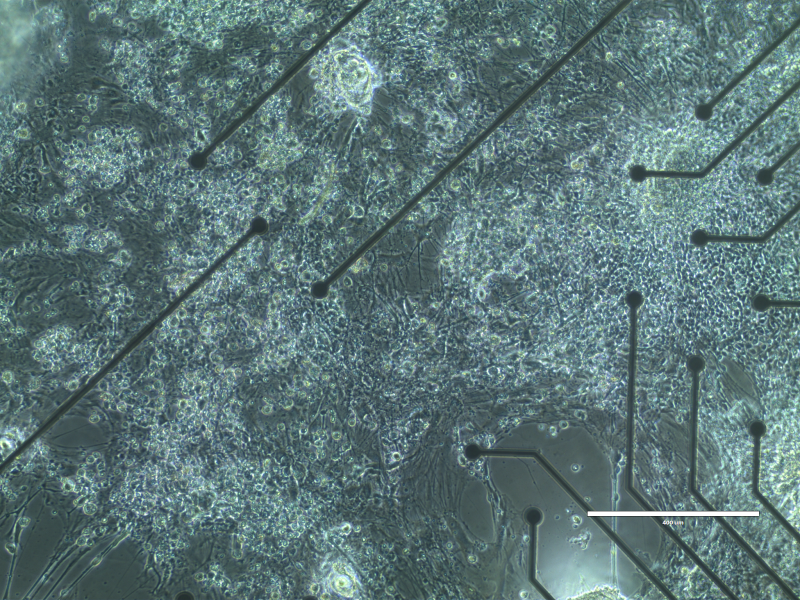

Neurons integrated with array

Credit: An Do and Zoran Nenadic, University of California, Irvine

A micrograph showing neurons integrated into a microelectrode array. The Do and Nenadic labs aim to create living engineered neural networks that can be used to repair damaged tissue in the brain.

There are no existing methods to fully restore function after a stroke. Stem cell therapies have yet to yield clinical results. Brain-computer interfaces and neuromodulation aim to improve neuronal behavior and function, but these methods either bypass the injury or rely heavily on the damaged brain.

With NSF support, researchers in the labs of An H. Do and Zoran Nenadic at the University of California, Irvine, are creating engineered neural networks: lab-grown tissues trained to recognize and decode brain signals. The team aims for their engineered neural networks to be able to communicate with the brain and eventually replace damaged tissue. This novel approach may one day serve as a therapy to help restore neural function to the cerebral cortex after a stroke.